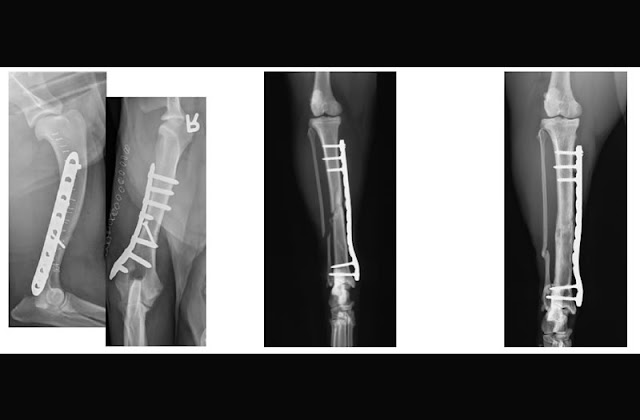

L’utilizzo di Placche e Viti

La riduzione con placca e viti, è un’ opzione chirurgica che viene utilizzata ampiamente (quando non siamo di fronte a traumi gravi) perchè presenta alcuni vantaggi:

– Riduzione anatomica dei frammenti soprattutto nelle fratture che interessano la superficie articolare.

– Precoce mobilizzazione dell’arto con riduzione del rischio di rigidità dell’articolazione.

![]() |

|

Placche e viti utilizzate nell’uomo |

Riduzione di una frattura con l’utilizzo di Placche e Viti nel Cane |